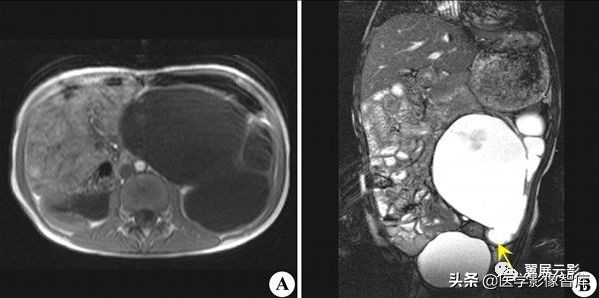

多囊肾

本病常合并多囊肝,此为先天性常染色体显性遗传性疾病,多数学者认为多囊肝是在多囊肾的基础上基因突变的结果,并定位于16号染色体上,也有学者认为该病是由于胚胎发育不良所导致,于胚胎早期管道形成时排列失常,导致无数迷管,于胚胎晚期未退化,且逐渐扩张成囊,成多发性囊肿病,根据发病年龄的不同,将其分为儿童型和成人型,本病多发生于双侧肾脏,可继发感染,结石以及囊内出血和囊壁钙化,也可以恶变,并有阻塞性黄疸及合并皮下囊肿的报道,临床上早期无症状,就诊时肾脏功能已经不同程度受损,肝功能受损程度较轻。

MRI表现为双肾增大和分叶状轮廓,多发囊肿多数为长T1长T2信号,出血性囊肿可为短T1长T2信号或长T1短T2信号,增强扫描所有病灶均不强化,应同时观察合并的多囊肝及胰脾多发囊肿。